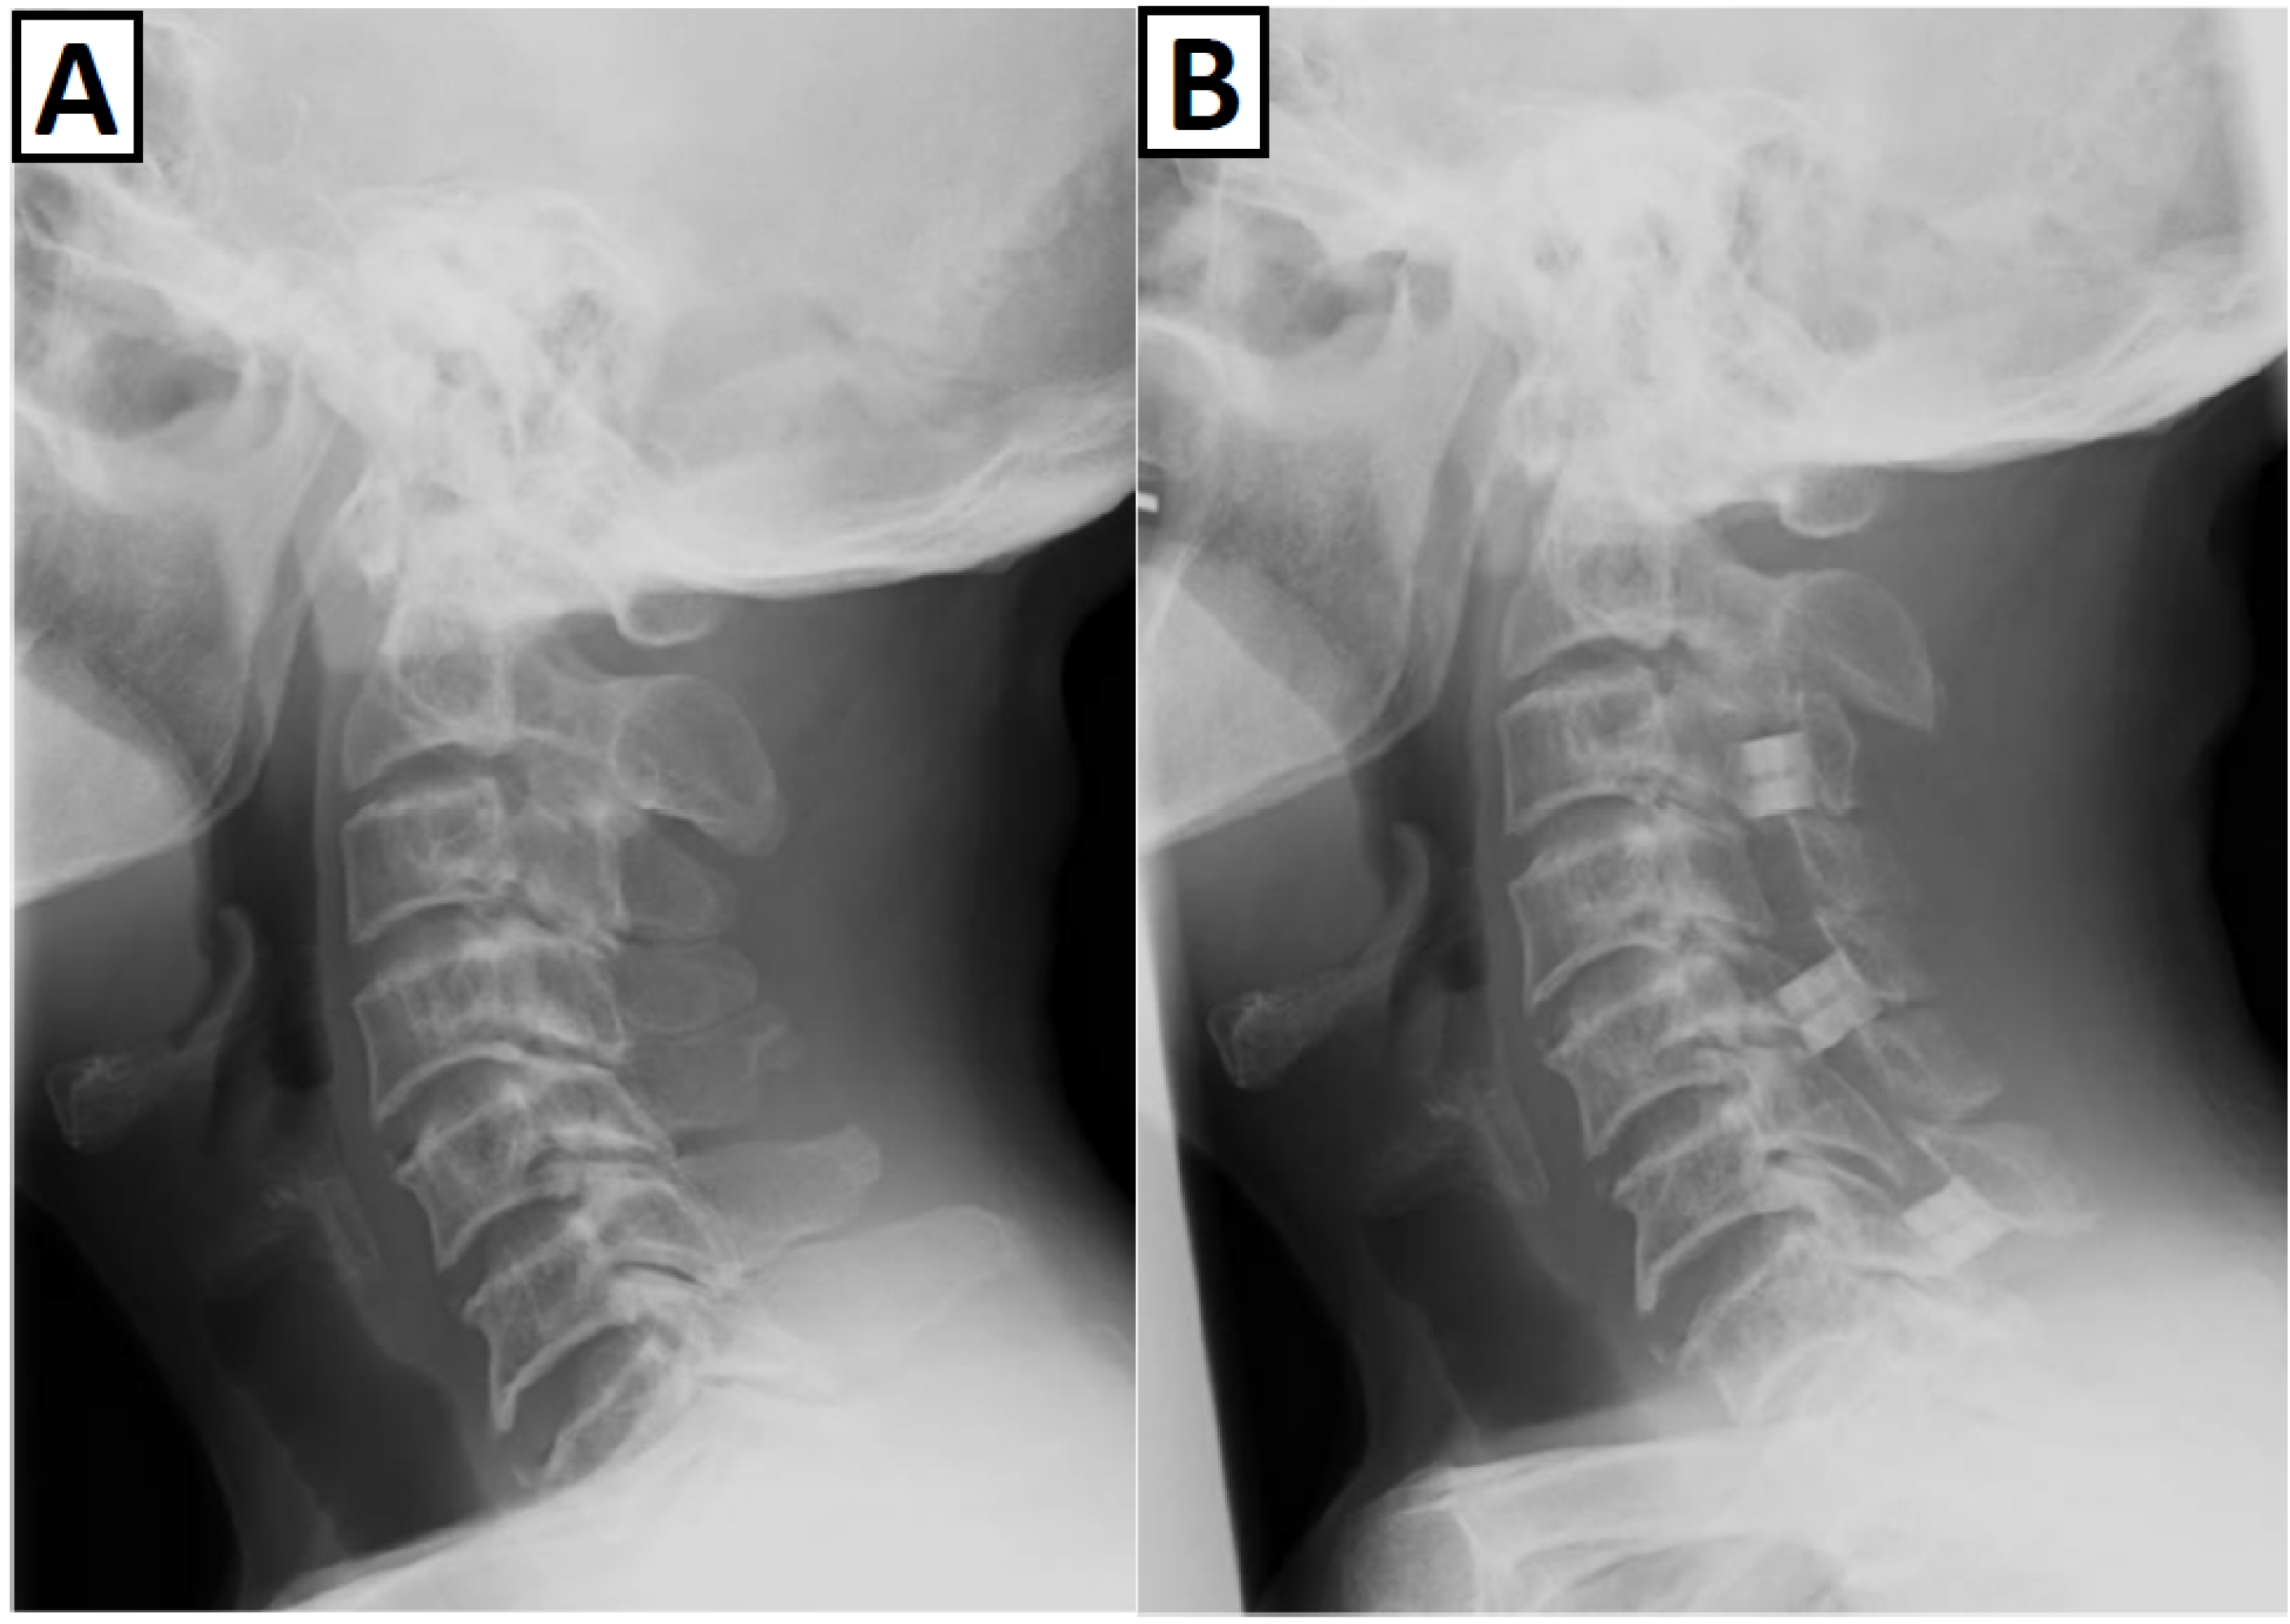

3.3. Spinal Complications